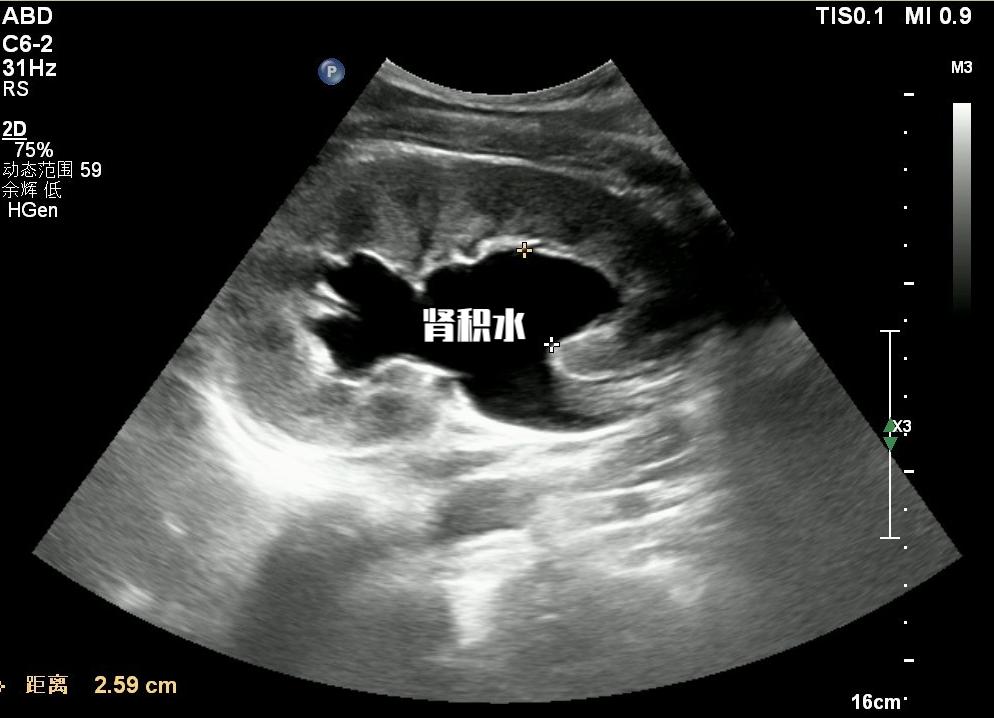

在这一过程中,膀胱内的压力开始增高, 当导致输尿管末端的活瓣作用丧失的时候,就会发现膀胱输尿管反流。就会逐步加重肾积水,慢慢的开始肾功能损害。

由于这一病程变化是一种慢性的过程,这个时候患者往往没有腰疼或者其他的不适,所以很多患者真当发现的时候, 往往肾功能已经受到不可逆的损伤! 甚至有部分患者需要接受血液透析治疗!